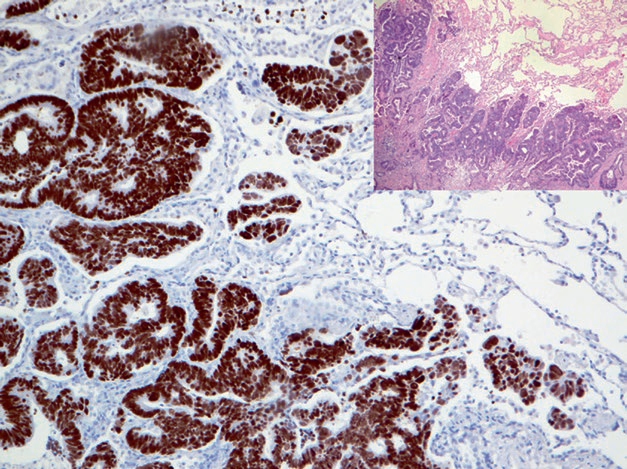

Figure 2. Rectal adenocarcinoma with lung metastasis, showing strong nuclear positive expression of SATB-2 in tumor cells.

Positive expression pattern: Nuclear

Recommended positive control tissue: Appendix